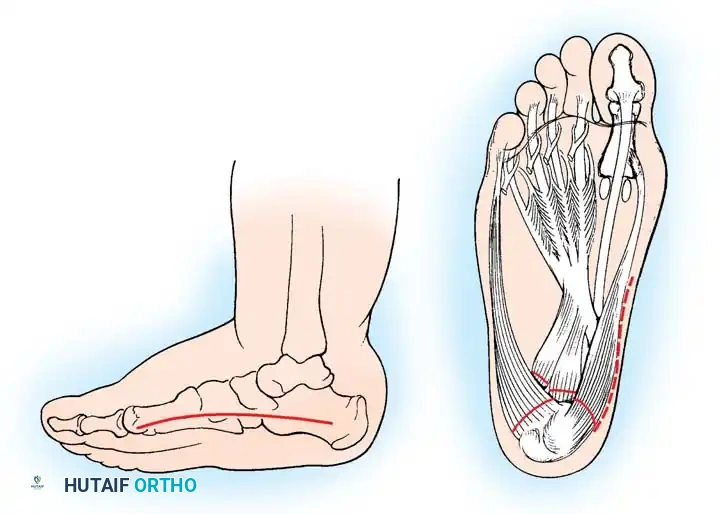

Fig. 32-22 Radical plantar-medial release and dorsal closing wedge osteotomy for cavovarus deformity. A, Incision. B, Release of musculotendinous mass.

Surgical Steps:

1. Incision: Make a generous curved incision over the medial aspect of the foot, extending anteriorly from the medial tuberosity of the calcaneus to the base of the first metatarsal.

2. Superficial Dissection: Identify the origin of the abductor hallucis muscle. Carefully separate it from its bony and soft-tissue attachments proximally and distally, leaving it attached only at its absolute origin and insertion.

3. Neurovascular Protection: Identify the posterior tibial neurovascular bundle as it divides into the medial and lateral plantar branches. Meticulous retraction is required as these structures enter the intrinsic musculature of the foot.

4. Deep Release: Identify the tendinous origin of the abductor hallucis at its attachment on the calcaneus (located between the medial and lateral plantar branches). Sever it to free the origin.

5. Plantar Fascia and Short Flexors: Sever the origins of the plantar aponeurosis and the flexor digitorum brevis from their attachments to the calcaneus. Gently dissect this entire musculotendinous mass distally and extraperiosteally as far as the calcaneocuboid joint.

6. First Metatarsal Osteotomy: If the first metatarsal remains rigidly plantarflexed after the soft-tissue release, proceed to a bony correction. Expose the base of the first metatarsal. Make a dorsally based closing wedge osteotomy immediately distal to the physis (in children) or the tarsometatarsal joint (in adults). Remove sufficient bone to correct the lateral talo-first metatarsal angle (Meary's angle) to 0 degrees.

7. Fixation: Secure the osteotomy with a smooth Steinmann pin or heavy Kirschner wires.

8. Closure: Close the wound in a routine fashion. Apply a well-padded short leg cast with the foot held in the corrected, plantigrade position.